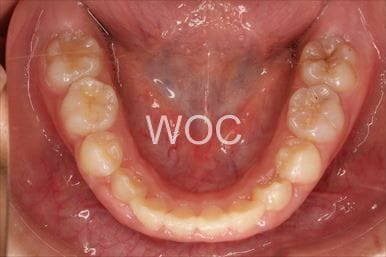

反対咬合

-

治療前1

-

治療前2

- 年齢:5歳5ヶ月

- 主訴:受け口

- 診断名:下顎前突、過蓋咬合

- 装置:可撤式拡大装置、機能的矯正装置

- 期間:5年4ヶ月 ※

- 費用:基本矯正料金:400,000円